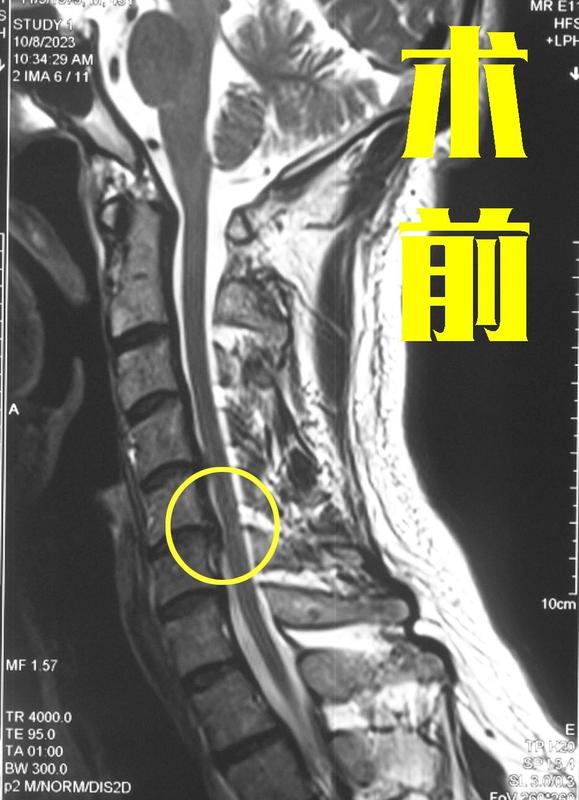

许多颈椎间盘突出症的患者除了身体上的痛苦外,心理上也是极其焦虑,尤其是担心手术问题,“医生让我手术,可我真的不想手术,就没有其他方法了吗?”甚至还有的患者学习能力很强,在网上查阅了很多的学术论文,想找到更好的治疗方法,但越看越焦虑,心理压力非常大,承受着身体、心理的双重折磨。最近,一位44岁的女性患者来到了宣武医院王作伟主任门诊,她是因为颈5-6出现的椎间盘突出前来就诊。据这位患者描述,她在2年前出现颈部疼痛,上肢尤其是右侧的疼痛、麻木,下肢略有无力的症状,当时去了当地医院查出来是颈椎间盘突出,并压迫到了脊髓、神经,于是建议她可以考虑手术。一上来就要手术,她开始觉得很荒谬,于是就服用了一些药物,没有接受其他治疗,但随后她的症状加重,于是开始在网上查阅相关资料和文献,看了一大堆后,反而让她越来越焦虑了,天天担心自己的病,吃不好也睡不好,脾气也不好了。上周,她的症状变得更加严重了,右手不能正常工作,下肢走路也出现了不稳,她这才又去了几家医院,但都是让手术,可她还是下不了决心。经过再三考虑后,她决定去北京的大医院再看看,最后才找到了王主任。术前影像学资料:其实,颈椎间盘突出大多情况不用手术!片子上显示有颈椎间盘突出是非常常见的,但只有患者出现明显的症状后,才需要治疗。颈椎间盘向正后方、侧后方等方向突出,就可能会压迫到神经根、脊髓、血管等重要组织,让患者出现相应的症状。其中,经常需要手术的情况是压迫到脊髓、神经根,一般患者出现脊髓压迫和脊髓损伤了,基本上都要手术,而神经根受压的患者仅有少数非常严重的,影响到日常生活和工作,保守治疗无效的情况才需要手术。而这位患者的情况就非常符合手术条件,如果不尽快手术,脊髓压迫进一步加重,后面治疗晚了很有可能造成不可逆的功能障碍,而如果不慎受到颈部外伤,还有可能加重脊髓受压,甚至有瘫痪可能,所以,像她这种情况一般建议积极手术。患者与其心理焦虑,不如尽快进行有效治疗!许多患者可能和这位患者一样,症状非常折磨人,试了其他方法没有效果,知道医生建议手术,但心里又害怕手术,非常纠结,迟迟不行动起来,让人陷入焦虑和内耗,对心理健康也产生了影响。其实,此类手术并不可怕,像这位患者的情况可以从颈前路做,手术是非常微创的,恢复也很快。这位患者和家人商量后,最终决定进行手术。手术由王主任亲自操刀,将突出的椎间盘切除,给脊髓、神经彻底减压,并给予内固定,手术成功完成。术后,患者的疼痛、麻木症状得到了极大缓解,术后第三天下肢走路已经比较稳健了。术后影像学资料:这位患者对治疗效果非常满意,心中的焦虑也随之消散了,心情格外的好。所以如果您也有类似的情况,不要郁结于心,积极行动起来,及时的正规治疗完全可以让您摆脱颈椎间盘突出带来的痛苦。